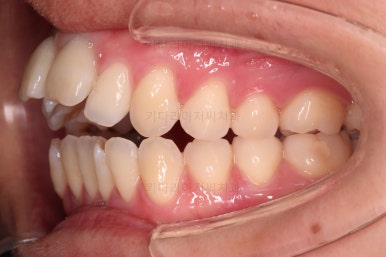

1. 초진

부산개방교합 키다리아저씨치과에 처음 내원 시 입안의 모습입니다.

전반적으로 치열이 삐뚤고요.

앞니쪽이 다물어지지 않는 개방교합(오픈바이트, open bite) 을 보였습니다.

어금니 맞물림을 보면 앵글씨 2급 부정교합 양상이어서 위아랫니가 모두 1대1로 부딪히고 있는 상태였습니다.